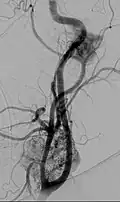

Digital subtraction arteriogram of carotid body tumor and jugular paraganglioma